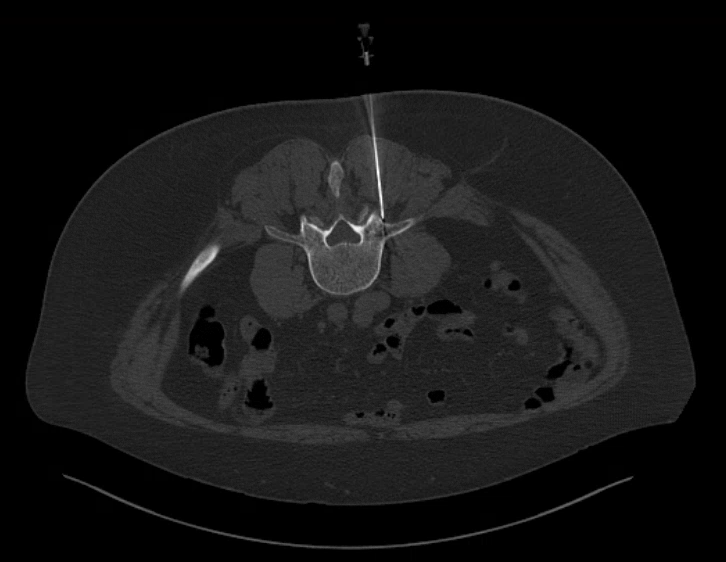

Chronic and complex pain syndromes such as complex regional pain syndrome (CRPS) can be difficult to diagnose and treat.

If this is suspected stellate ganglion block and lumbar sympathetic block can be performed to improve symptoms.

Advanced Nerve Blocks

Using high precision ultrasound and CT guidance, our experts are able to block deep nerves throughout the body. These are often performed as a test to determine which nerves are responsible for pain. Once a site is identified, it is targeted for further treatment using one of the more long lasting techniques. Targets include the coeliac plexus, stellate ganglion, lumbar sympathetic plexus, trigeminal nerve and others.